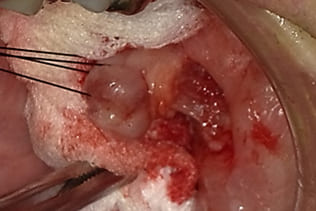

局所浸潤麻酔を行い、腫瘍に糸をかけ、十分にカウンタートラクションをかけた状態で、メスで腫瘍に沿って木の葉状に切開し、牽引しながらメスで周囲の結合組織と腫瘍の境界を鋭利に剥離する。切る感じではなくて削ぐ感じでメスを用いることが重要である。

摘出物:線維腫 Fibromaの診断でした